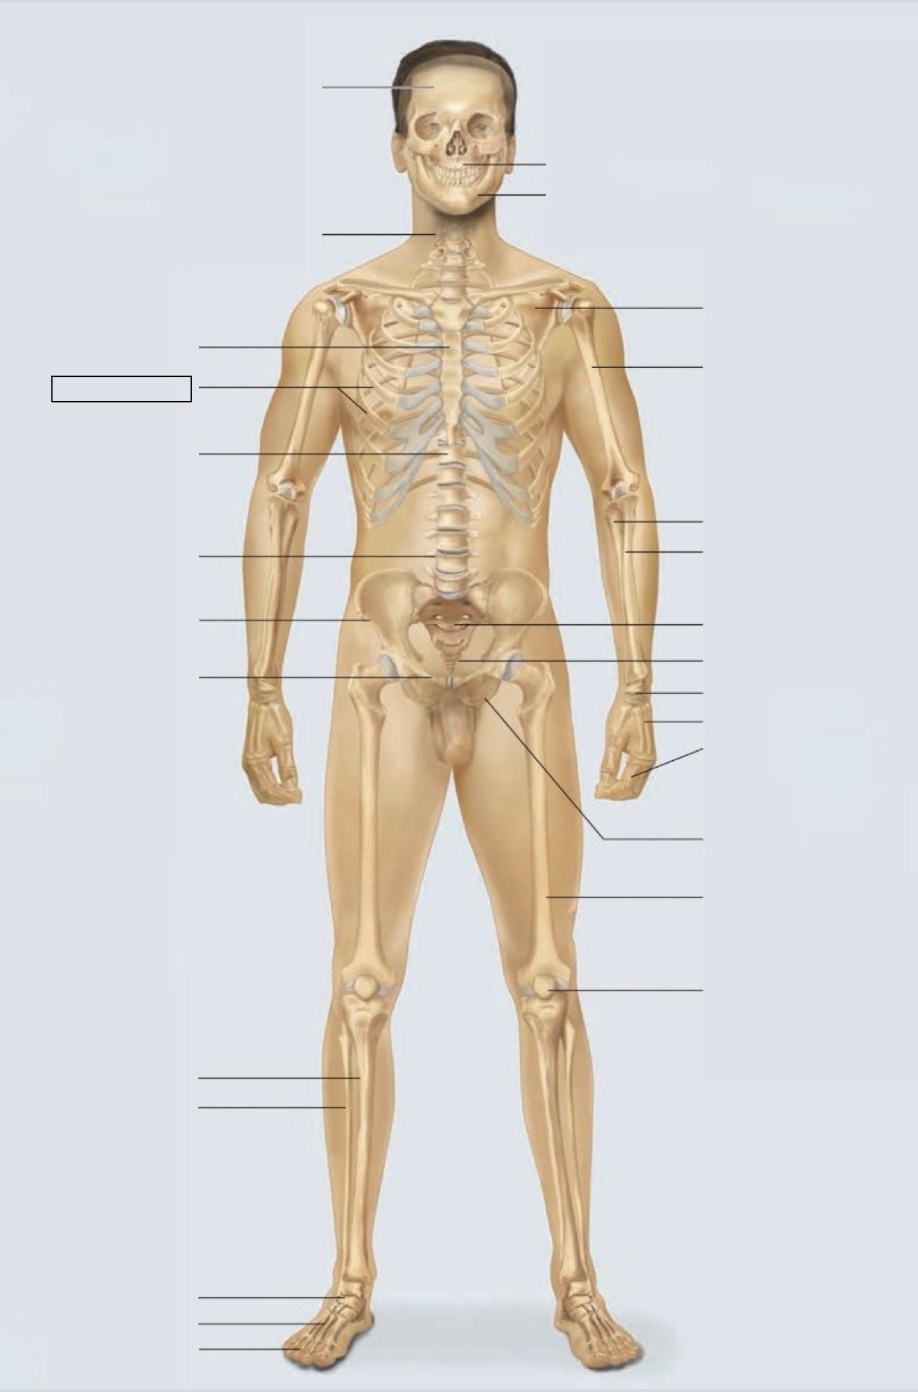

maxilla

mandible

scapula

humerus

ulna

radius

sacrum

coccyx

carpals

metacarpals

phalanges

ischium

femur

patella

phalanges

metatarsals

tarsals

fibula

tibia

pubis

ilium

lumbar vertebrae (L4)

thoracic vertebrae (T11)

ribs

sternum

cervical vertebrae

skull